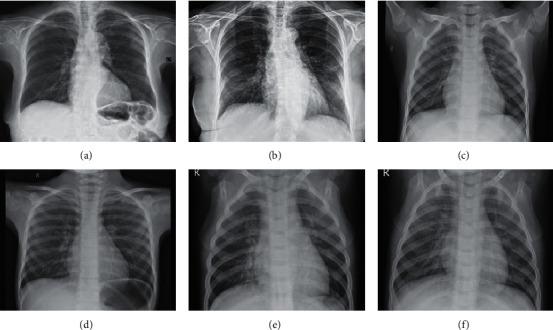

Since the outbreak of Coronavirus disease 2019 (COVID-19), it has been spreading rapidly worldwide and has not yet been effectively controlled. Many researchers are studying novel Coronavirus pneumonia from chest X-ray images. In order to improve the detection accuracy, two modules sensitive to feature information, dual-path multiscale feature fusion module and dense depthwise separable convolution module, are proposed. Based on these two modules, a lightweight convolutional neural network model, D2-CovidNet, is designed to assist experts in diagnosing COVID-19 by identifying chest X-ray images. D2-CovidNet is tested on two public data sets, and its classification accuracy, precision, sensitivity, specificity, and 1-score are 94.56%, 95.14%, 94.02%, 96.61%, and 95.30%, respectively. Specifically, the precision, sensitivity, and specificity of the network for COVID-19 are 98.97%, 94.12%, and 99.84%, respectively. D2-CovidNet has fewer computation number and parameter number. Compared with other methods, D2-CovidNet can help diagnose COVID-19 more quickly and accurately.

自 2019 年冠状病毒病(COVID-19)爆发以来,它在全球范围内迅速传播,尚未得到有效控制。许多研究人员正在从胸部 X 光图像研究新型冠状病毒肺炎。为了提高检测精度,提出了两个对特征信息敏感的模块,双路径多尺度特征融合模块和密集深度可分离卷积模块。基于这两个模块,设计了一个轻量级卷积神经网络模型 D2-CovidNet,通过识别胸部 X 光图像来辅助专家诊断 COVID-19。D2-CovidNet 在两个公共数据集上进行了测试,其分类准确率、精度、灵敏度、特异性和 1 分分别为 94.56%、95.14%、94.02%、96.61%和 95.30%。具体来说,该网络对 COVID-19 的准确率、灵敏度和特异性分别为 98.97%、94.12%和 99.84%。D2-CovidNet 的计算数量和参数数量较少。与其他方法相比,D2-CovidNet 可以帮助更快速、准确地诊断 COVID-19。